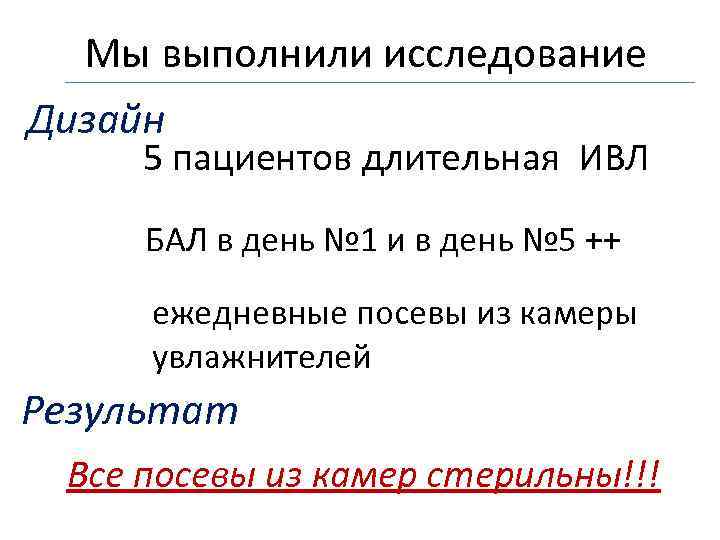

Мы выполнили исследование Дизайн 5 пациентов длительная ИВЛ БАЛ в день № 1 и в день № 5 ++ ежедневные посевы из камеры увлажнителей Результат Все посевы из камер стерильны!!!

Мы выполнили исследование Дизайн 5 пациентов длительная ИВЛ БАЛ в день № 1 и в день № 5 ++ ежедневные посевы из камеры увлажнителей Результат Все посевы из камер стерильны!!!